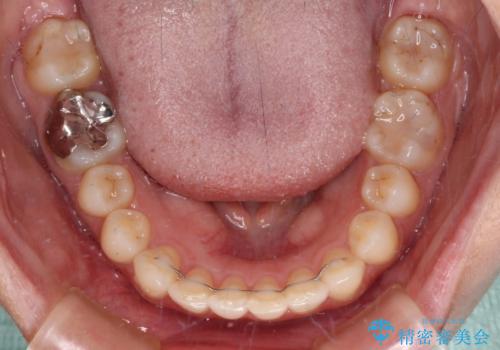

上下ともにデコボコの程度は著しいものではなく、インビザラインで十分に対応可能な歯列不正でした。

後戻りによりスペースができてしまうことを避ける目的で、IPR(歯と歯の間を削る)を極力用いない矯正治療を行うこととしました。

インビザラインであれば来院間隔が多少長くなってもワイヤー矯正ほど問題とならないため、遠方からの通院であっても中断や転院せずに治療を行うことができます。